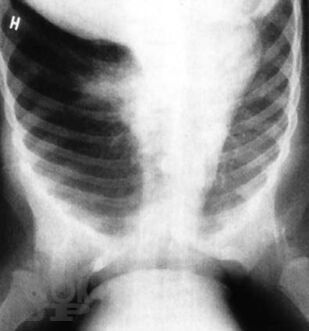

В монографии представлены важнейшие хронические заболевания легких у детей, рассмотрены вопросы терминологии и классификации этих болезней. Описаны клинические проявления различных форм хронической бронхолегочной патологии, даны критерии и современные методы диагностики. Отдельные главы посвящены хроническим воспалительным заболеваниям легких, врожденной и наследственной патологии, бронхиальной астме, интерстициальным болезням легких, грибковым поражениям бронхолегочной системы. Рассмотрены особенности течения туберкулеза при хронических неспецифических заболеваниях легких. Изложены принципы терапии хронических заболеваний легких у детей. Книга адресована педиатрам, пульмонологам, аллергологам, врачам общей практики, сотрудникам научно-исследовательских учреждений и учебных заведений.